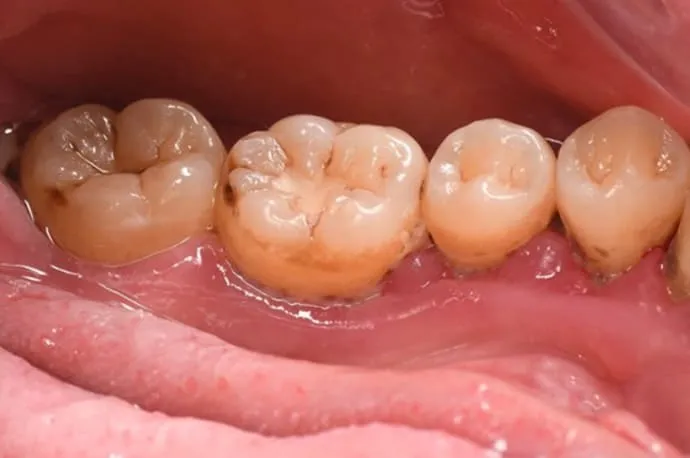

歯周基本治療の症例

治療前

治療後

歯周基本治療後の状態です。治療により歯ぐきの腫れや出血が改善し、炎症が落ち着いている様子が確認できます。歯石の除去によって、口臭やお口の中の不快感も軽減しています。

※歯周病によって歯ぐきが腫れていた場合、炎症が治まることで歯ぐきが引き締まり、治療前より下がったように見えることがあります。

※歯石除去後、一時的に知覚過敏の症状が出る場合があります。